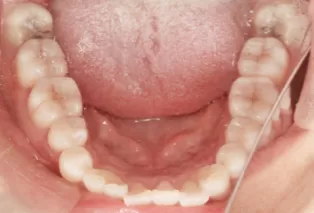

Intraoral photos